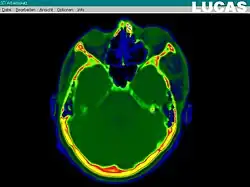

The most important component for CAS is the development of an accurate model of the patient. This can be conducted through a number of medical imaging technologies including CT, MRI, x-rays, ultrasound plus many more. For the generation of this model, the anatomical region to be operated has to be scanned and uploaded into the computer system. It is possible to employ a number of scanning methods, with the datasets combined through data fusion techniques. The final objective is the creation of a 3D dataset that reproduces the exact geometrical situation of the normal and pathological tissues and structures of that region. Of the available scanning methods, the CT is preferred,[1] because MRI data sets are known to have volumetric deformations that may lead to inaccuracies. An example data set can include the collection of data compiled with 180 CT slices, that are 1 mm apart, each having 512 by 512 pixels. The contrasts of the 3D dataset (with its tens of millions of pixels) provide the detail of soft vs hard tissue structures, and thus allow a computer to differentiate, and visually separate for a human, the different tissues and structures. The image data taken from a patient will often include intentional landmark features, in order to be able to later realign the virtual dataset against the actual patient during surgery. See patient registration.

Image analysis and processing

Image analysis involves the manipulation of the patients 3D model to extract relevant information from the data. Using the differing contrast levels of the different tissues within the imagery, as examples, a model can be changed to show just hard structures such as bone, or view the flow of arteries and veins through the brain.